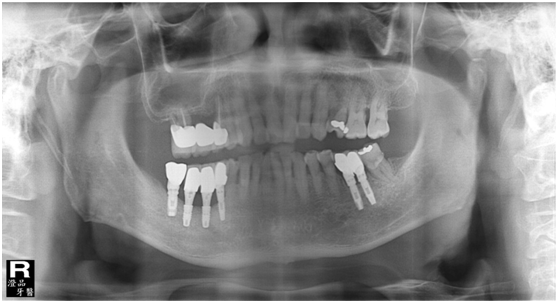

患者的原始片 91/06/13

患者陳先生於91/06/03初診,為一個牙周病患者,合併有右下缺牙。經過保守性牙周處理後,於91/08/14放置右下三顆植體。

完成後大約半年至一年進行一次例行性追蹤檢查,並無特別問題。以下為96/08/13時的追蹤小片,可以見到當時三顆植體的骨高度並無顯著變化。但右下第一小臼齒此時發現有搖動度增加的情形,當時對該顆牙做了咬合調整,降低咬合功能負荷,希望能有所改善。

96/08/13